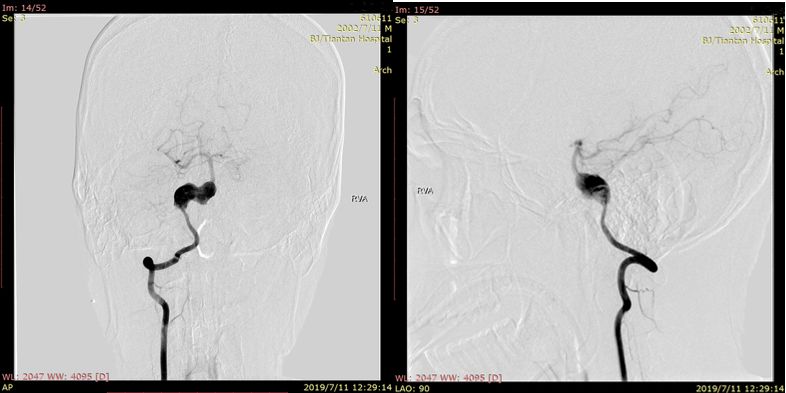

术前右椎动脉造影显示:基底动脉中下段夹层动脉瘤。

术前右椎动脉3D造影

术前左椎动脉造影显示:基底动脉中下段夹层动脉瘤,左侧小脑后下动脉夹层动脉瘤。